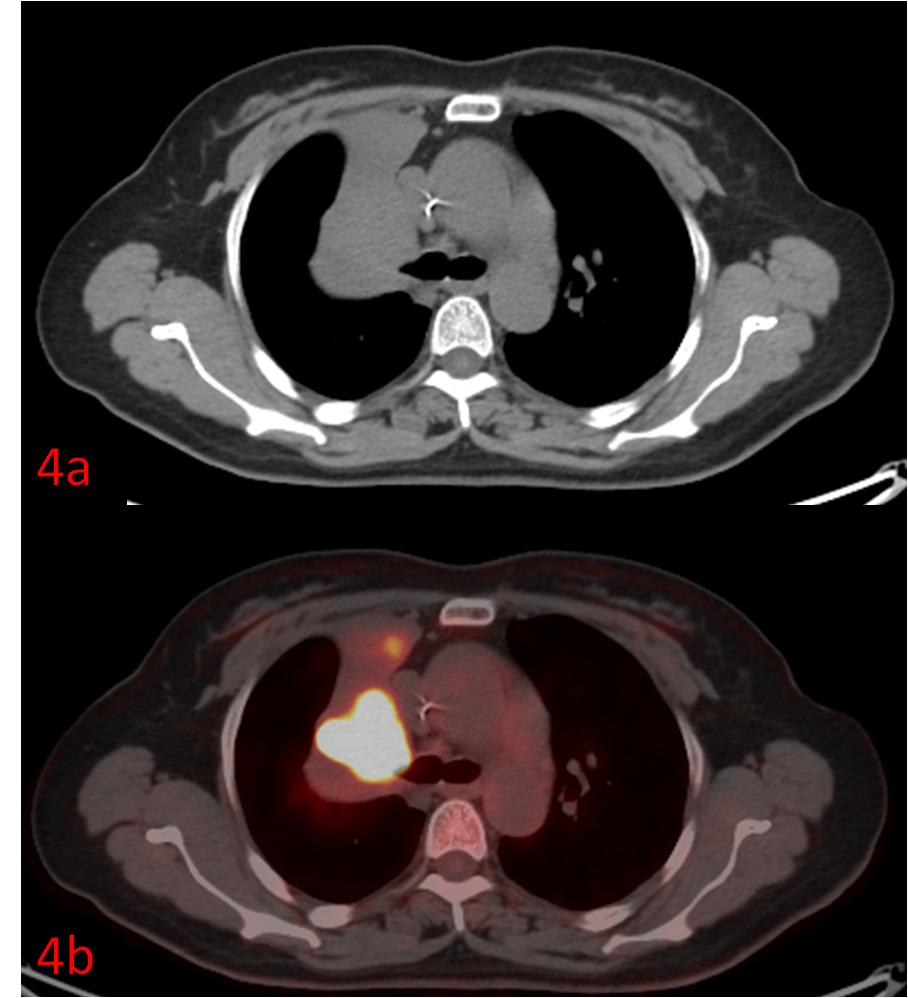

例4:中年女性,右肺上葉小細胞癌伴右肺上葉不張、阻塞性炎癥,常規(guī)CT無法區(qū)分腫瘤和不張的肺組織(圖4a),PET/CT清晰展示了腫瘤的邊界(圖4b)。